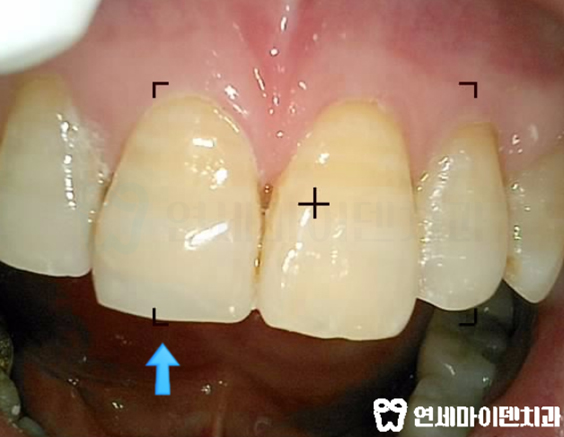

앞니 레진 떨어져 나간 부위가 보이시죠?

벌써 두 번째 떨어진거라 스트레스도 많이 받으셨어요 ㅜㅜ

연세마이덴치과에서 앞니 재치료로 레진을 다시 접착해드렸습니다.

어떠신가요?

옆 치아와 비슷한 색과 모양으로 완성이 되었습니다.